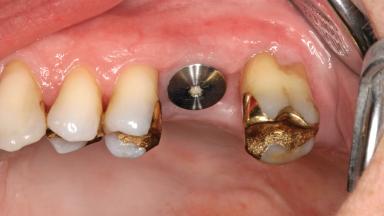

The patient was an 87-year-old woman with no general diseases, no medication, no allergies, and a non-smoker. Her maxillary left first molar had been extracted 6 weeks previously due to a root fracture. The clinical examination revealed a complete dentition, except for the maxillary left first molar, which was missing. Generalized but mild horizontal bone loss without any pathologic periodontal pockets was observed. Oral hygiene was good. Both the second premolar and the second molar had been restored with adequate gold inlays and showed 2 mm of gingival recession facing the edentulous site. The course of healing had been uneventful after extraction of the maxillary left first molar, and the width of the alveolar process was intact.